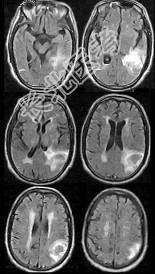

- 单项选择题男,76岁, 突发神志不清,伴呕吐6小时, MRI检查如图所示,最可能的诊断为 ( )

A、出血性脑梗死

B、肿瘤出血

C、原发脑出血

D、脑结核

E、脑脓肿